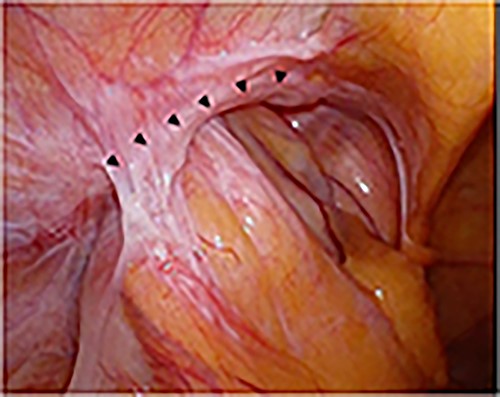

Intraoperative findings; the sigmoid colon entered into the hernial orifice as a sliding hernia; the black triangles indicate the hernial orifice.

Intraoperative findings of the left inguinal region after peritoneal incision; the black triangles indicate the hernial orifice; the dotted circle indicates the assumed hernia sac; the black cross indicates the internal inguinal ring.